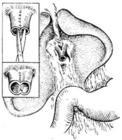

3、对肝门处狭窄,尤其是双侧肝管开口狭窄,应解剖肝门,显露狭窄处以上2cm肝管,或作肝方叶部分切除显露。切开时应跨过狭窄上下端,必要时予以整形,扩大胆管腔,甚至需要切开胆(肝)总管、左或(和)右肝管,与Y型空肠侧-侧或端-侧吻合,要求尽可能取净近端胆管内结石,提高手术效果。

术方式的选择:对医源性胆管狭窄采用的狭窄疤痕切除、胆管对端吻合术,由于其再狭窄率高,近年已放弃不用。采用狭窄段纵行切开后,用带血管蒂空肠瓣、胃壁瓣、圆韧带等行修复,文献偶有报道,可根据情况选择使用。现多采用狭窄近端胆管空肠Roux-en-Y吻合。